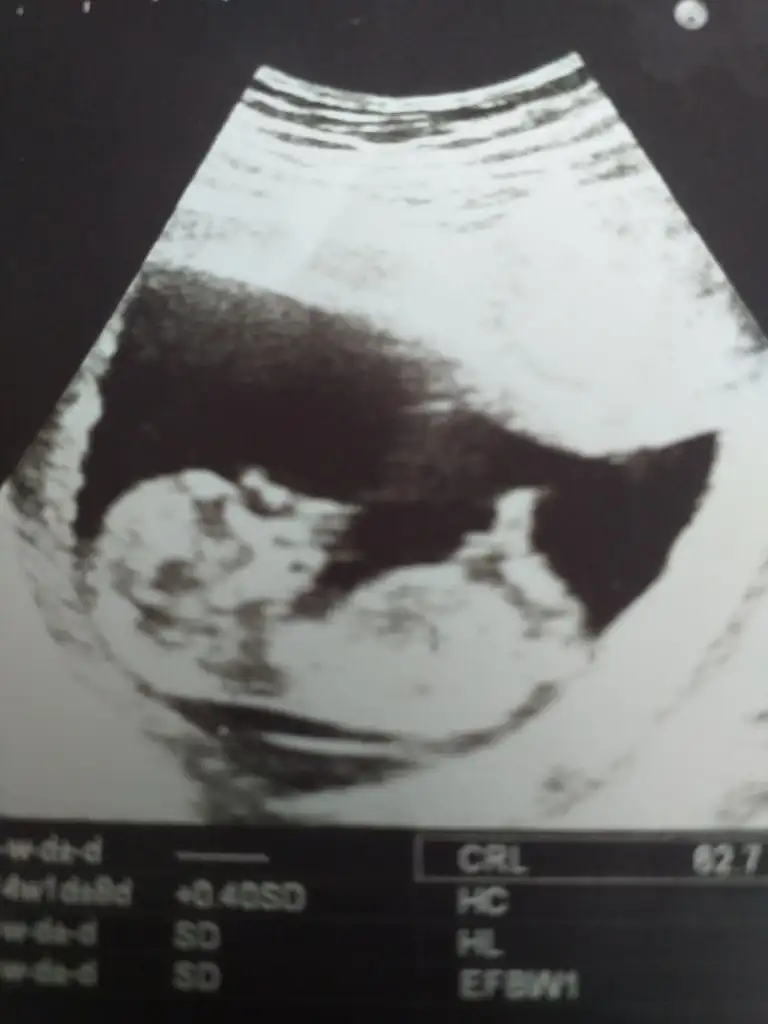

3 yorumunda erkek oldu 3 ayrı ultrason fotosunda bir kızım var hayırlısı olur inşallah doktor söylemedi cinsiyet bizim şubat grubunda herkese söylemiş doktorları bi ben öğrenemedim teşekkür ederim sağolErkek gibi

Erkek dediErkek gibi nubu kafa şekli kız gibi13 hafta olursa paylaşın teyit ederim ❤

Bilmişim sağlıkla gelsinErkek dedi